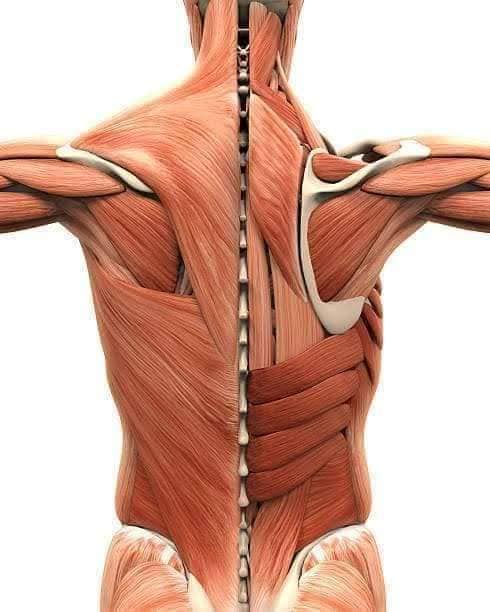

Спинні м'язи

Спинні м'язи виконують функції підтримки хребта, а також дозволяють здійснювати рухи тулуба.

Поверхневі спинні м'язи

М'язи, що піднімають лопатку: Трапецієподібний м'яз: великий м'яз, що покриває верхню частину спини. Його функція - підтримка і рух лопаток, а також забезпечення стабільності хребта.

М'язи, що ведуть лопатку до хребта: Широкий м'яз спини: великий м'яз, що розташований в нижній частині спини. Він відповідає за рухи плечей і лопаток, а також за розширення верхньої частини тулуба.

Глибинні спинні м'язи

М'язи, що забезпечують стабільність хребта: М'язи, що розташовані між хребцями: включають мускулатуру, яка забезпечує стабільність і підтримку хребта, а також дозволяє здійснювати рухи хребта.

М'язи, що здійснюють ротацію та нахили

М'язи, що забезпечують ротацію хребта: Ротаційні м'язи: допомагають у здійсненні обертальних рухів тулуба, а також у підтримці рівноваги і стабільності хребта.